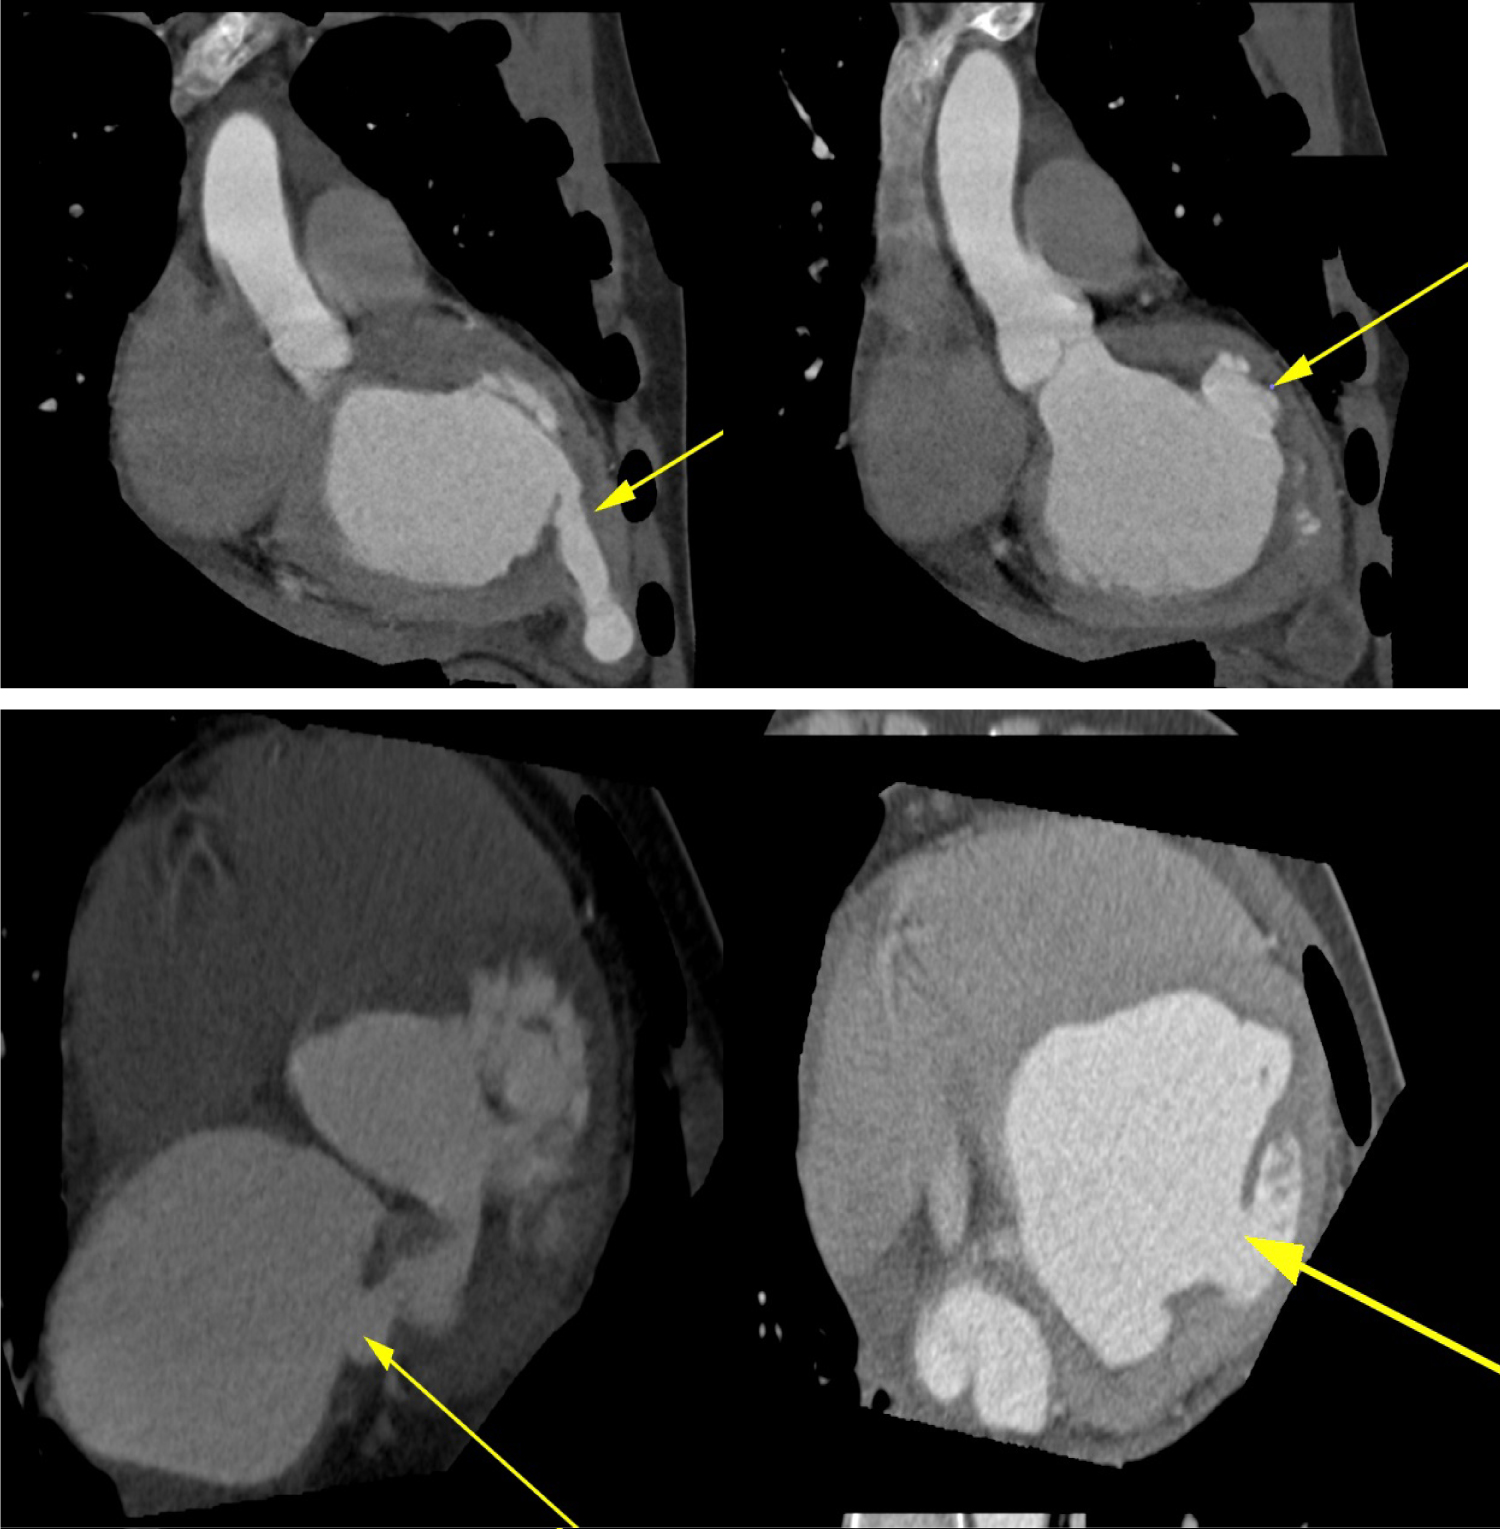

Upon arrival to the cardiology clinic, the patient was noted to be hemodynamically stable with a blood pressure of 126/83 mmHg and heart rate of 88 beats/min. He was not in heart failure. He had a displaced, volume overloaded apex beat and a grade 5/6 pan-systolic mitral regurgitation murmur. Twelve lead electrocardiograms showed sinus rhythm with wide P wave suggestive of left atrial enlargement and early repolarisation. His blood parameters revealed improved Haemoglobin at 11.1 g/dl, CRP of 37 mg/l and a normal urea and electrolytes. He underwent trans-thoracic echocardiography (TTE), which revealed a left ventricular end-diastolic diameter of 62 mm and left ventricular end- systolic diameter of 34.7 mm with an EF of 65%. Right ventricular systolic function was preserved with a trans-annular planar systolic excursion of 2.6 cm and RV S' velocity of 15.5 cm/s. There was severe eccentric mitral regurgitation and severe tricuspid regurgitation with an estimated pulmonary artery systolic pressure of 82 mmHg. No masses or vegetation's were noted. Two discrete aneurysms were noted, one just below the mitral annulus inferior to the posterior mitral leaflet (PML) and the second at the apex of the left ventricle (Figure 1). The patient subsequently underwent two dimensional and three- dimensional transoesophageal echocardiogram (TEE) which confirmed the presence of sub-mitral aneurysm and apical aneurysm. There was spontaneous echo contrast and thrombus in the sub-mitral aneurysm (Figure 2). The PML was perforated revealing two mitral regurgitation jets, one through the perforation and the second was central in origin (Figure 3 and Figure 4). There was also suspicion of oscillating mass on the PML (Figure 3). His blood cultures remained negative. The gene expert for Tuberculosis was negative. He tested negative for syphilis, Human immunodeficiency virus, connective tissue disease and sarcoidosis using the Treponema Haemagglutination test, HIV serology, antinuclear antibody test and serum angiotensin converting enzyme assays, respectively. The patient underwent Multi-detector Computed Tomography (MDCT) to define in detail the anatomical course of the aneurysms and also to exclude coronary artery disease. Multiple left ventricular aneurysms were noted in the posterior wall and the apex (Figure 5 and Figure 6). Aneurysm in the mid-postero-lateral wall measured 38.9 mm × 16.6 mm, sub-mitral aneurysm with thrombus in situ, measured 57.5 mm × 37.8 mm and it dipped inferior to the left atrium (Figure 6). The apical aneurysm in the inferior aspect was calcified at the antero-lateral margin and measured 54.4 mm × 12.7 mm, and in the septal aspect measured 26.9 mm × 14.7 mm. A discrete perforation was noted in the PML measuring 11.1 mm in diameter (Figure 5). There was no significant mediastinal lymphadenopathy.

Figure 5: Multi-Detector cardiac computed Tomography showing multiple left ventricular aneurysms at the base, posterior wall, postero-lateral wall and the apex (top and bottom panels, yellow arrows) and perforation in the posterior mitral leaflet (bottom left, yellow arrow). View Figure 5

Figure 6: Multi-Detector Cardiac Computed Tomography showing thrombus in the submitral and apical aneurysms (Top panels). Three-dimensional reconstruction (bottom panel) depicting multiple aneurysms of the left ventricle. View Figure 6

Initial TTE imaging revealed mitral regurgitation due to prolapse of PML and concurrent sub-mitral aneurysm as well as apical aneurysm, but further definition of the aneurysm extent and presence of vegetation's was not possible. TEE proved useful in further confirming the aneurysms [9]. Three-dimensional TEE was useful in assessing the morphology of the valve and the enface view showed a clear perforation in the P1 segment of the PML [10]. On multiplane 3D reconstruction the area of the defect in the PML could be measured. Further, two distinct MR jets were visualised on 2D and 3D TEE. One was central due to annular dilation and the second eccentric jet was noted to be coming through the perforation, hence, confirming the presence of a true defect in the mitral valve and not merely an artifact. The suspicion of oscillating mass was raised after TEE imaging due to the superior imaging quality and good temporal resolution of TEE. Finally, MDCT through its good spatial resolution enabled visualisation of the location and anatomy of the aneurysms as well as presence of clear perforation in the PML [11]. It also non-invasively confirmed normal coronary anatomy, thus excluding this as a cause of the left ventricular aneurysms. It established presence of thrombus in the sub-mitral and the apical aneurysm which was not clearly delineated on TEE.